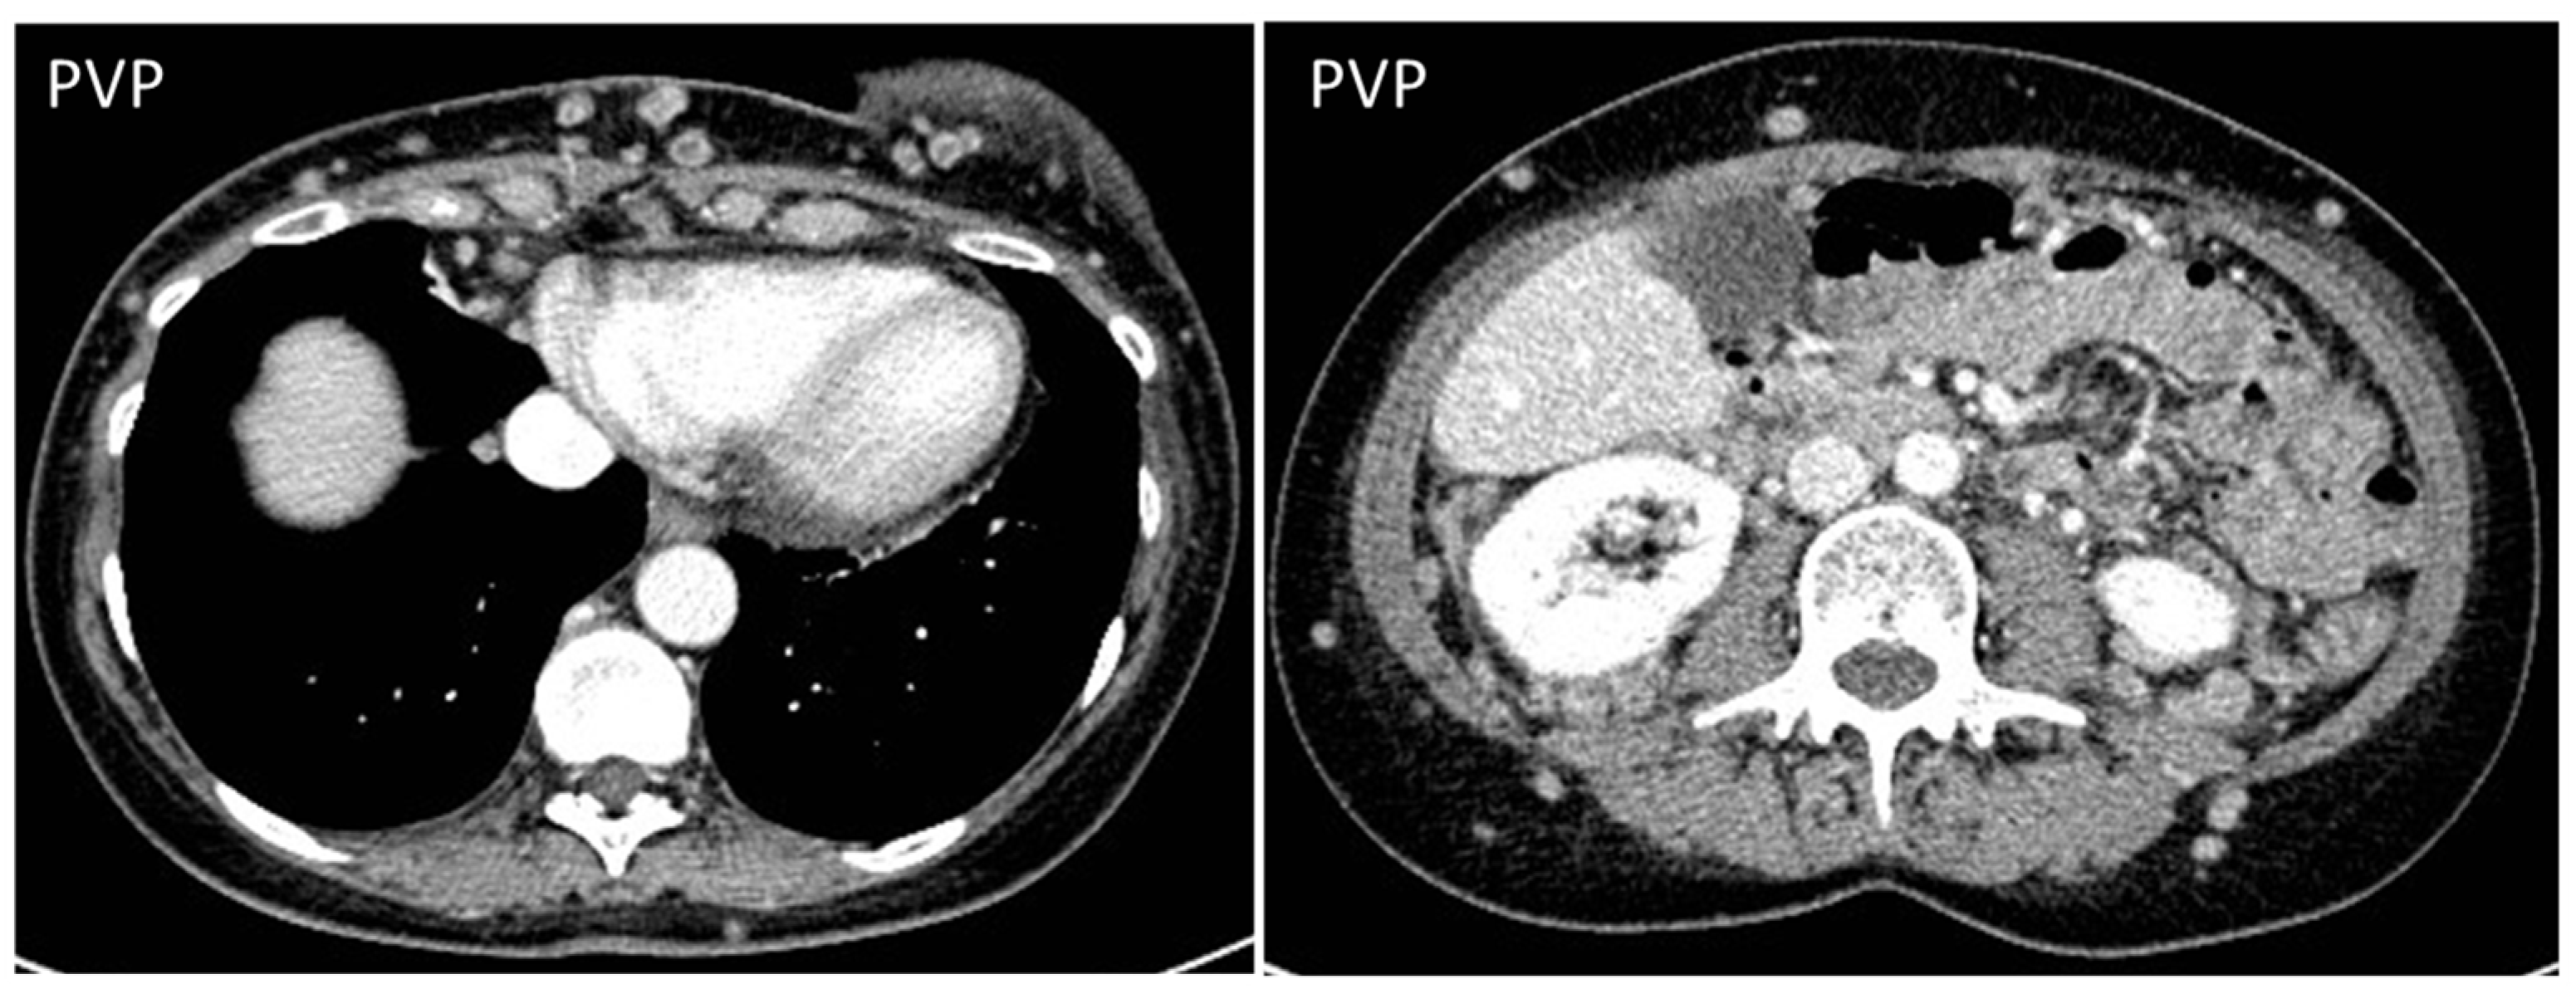

- Desmoplastic Small Round Cell Tumor (DSRCT): rare, highly aggressive sarcoma of adolescents, which primarily involves the serosal surfaces of the abdominal cavity infiltrating the abdominal wall [30,31,32]. Classic findings include bulky multiple, hypoattenuating, soft-tissue masses, with omental, serosal, and rectovesical involvement [31,32] and typical punctate or amorphous calcifications [32]. Modest heterogeneous enhancement is seen on arterial phase, without prolonged enhancement or portal washout [31,32] (Figure 10). On MR, DSRCTs are heterogeneously iso- to-hypointense on T1-w images, with hyperintense foci due to intratumoral hemorrhage [32].